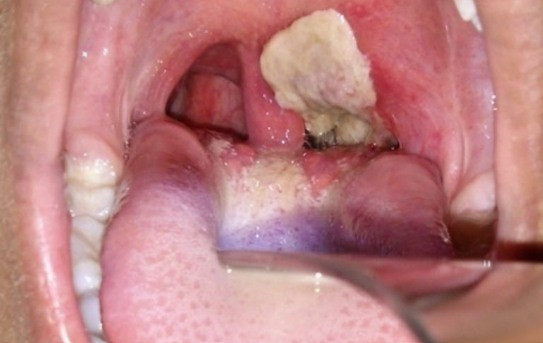

Đường hô hấp tắc nghẽn gây khó thở: Hầu hết các triệu chứng bệnh bạch hầu chủ yếu là gây viêm họng, đau họng, tổn thương thanh quản. Vi khuẩn bạch hầu sẽ tạo lớp giả mạc màu trắng ngà do các mô tế bào bị viêm tạo ra lớp màng giả mạc bám chặt vào trong vòm họng.

Nếu không được điều trị, mảng giả mạc này sẽ phát triển và lan rộng lấp đường hô hấp gây khó thở, ngạt thở, suy hô hấp cho người bệnh.